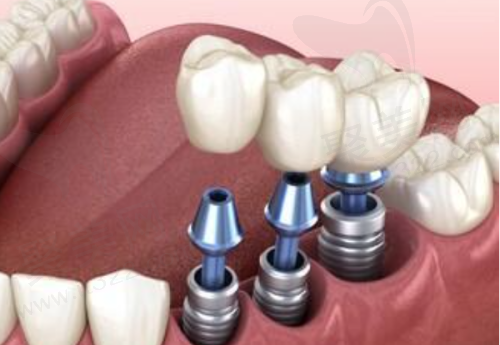

在寻求修复缺牙的过程中,许多人都会考虑种植牙这一解决方案。其中,即拔即种植牙作为一种新兴的技术,因其能够在患者拔牙后立即进行种植,受到了越来越多人的关注。然而,面对这种快速解决方案,也不可避免地会有人质疑其成效和适用性。本文将从即拔即种植牙的优势与缺陷进行深入探讨,帮助读者了解这一技术适合哪些人群,并尽可能全方面地呈现其相关知识与信息。

即拔即种植牙技术的较大优势在于能够大大缩短治疗时间。传统的种植牙修复通常需要分多个阶段进行,而即拔即种则允许患者在拔牙后立即进行种植,减少了多次就诊的麻烦和痛苦。这种方法特别适合那些希望尽快修复口腔功能的患者,尤其是年轻人和工作忙碌的上班族。

此外,即刻种植还能有效减少牙槽骨的吸收。在拔牙后,牙槽骨会面临一定程度的吸收,而即刻种植则通过立即植入种植体帮助保持牙槽骨的形态和高度,这对后期的种植成效至关重要。